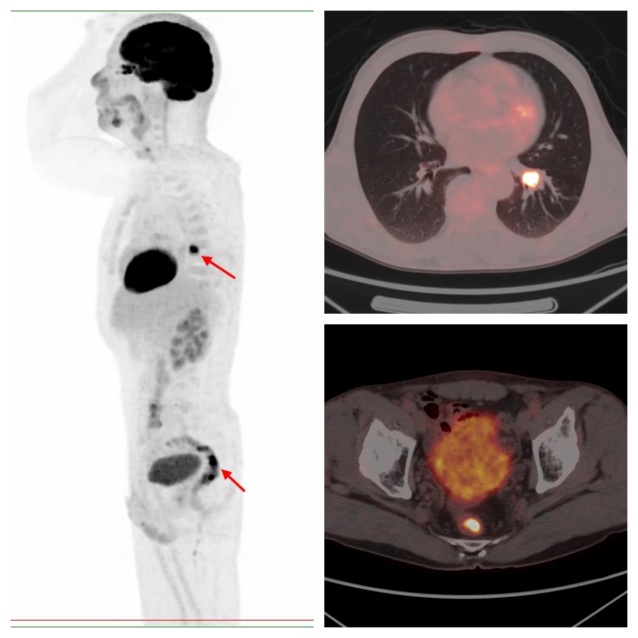

在臨床工作中,由于癥狀不典型、檢查技術(shù)受限、檢查不全面等多方面原因,容易發(fā)生只診斷1種原發(fā)癌,而忽視其它多原發(fā)癌的情況。PET/CT全身掃描能夠?qū)Ⅲw內(nèi)存在的代謝異常病灶完整的展示出來,就好比“點(diǎn)亮”一般,代謝異常區(qū)暴露無遺,很容易的就能被觀察出來,給診斷帶來線索,非常有利于全面檢出多種腫瘤。

病例2,PET/CT示左肺下葉、直腸代謝異常,符合雙原發(fā)癌;之后患者行支氣管鏡下活檢,病理證實(shí)原發(fā)肺鱗癌;行腸鏡下活檢,病理證實(shí)為原發(fā)直腸潰瘍型腺癌。